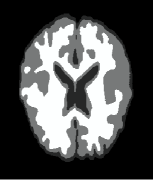

Example 3: real-world images. Test our method in two real-world images, i.e., camera man and MRI (magnetic resonance imaging) brain image which comes from medical imaging subject, see Fig. 4. We first test our method in noisy images and images with information lost. In Fig. 4, the variance used for adding noise is 0.01, and the percentage of information lost is . The conclusions we get are very close to those obtained when we test the methods in synthetic images in examples 1 and 2. From the rows one and three of Fig. 4, we see that all the methods give very good results in segmenting the two original real-world images. But for the images with information lost especially for the image in Fig. 4(A4), the results of methods [43, 23] are worse than the results of methods [6] and ours, see Fig. 4(B4), (C4), (D4), and (E4). Moreover, for the results of methods [6] and ours, we see that our result gives much more details for the white matter, see Fig. 4(D4) and (E4).

| (A4) | (B4) [43] (68.27) | (C4) [23] (74.28) | (D4) [6] (86.11) | (E4) Our (95.66) |